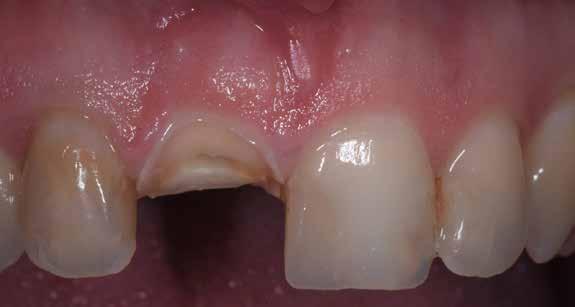

A korai harmicas éveiben járó hölgy rendelőnkbe érkezésének oka a jobb felső nagymetsző fog bizonytalan érzkenysége, elmondása alapján gyermekkorában trauma érte a felső frontrégiót. A frakturált klinikai koronákat kompozittöméssel helyreállították, egyéb kezelést akkor nem tartottak szükségesnek. Az utóbbi hónapokban tapasztalt érzékenység miatt kereste fel rendelőnket. A klinikai vizsgálat (1. és 2. kép) és a CBCT felvétel (3. kép) alapján diagnosztizált külső gyökérreszorpció megoldására a fog eltávolítását, implantátum

bukkális 1. kép: Kiindulási állapot, 2020. január. 3. kép: Kiindulási CBCT felvétel. 2. kép: Kiindulási állapot a palatinális oldal felől.